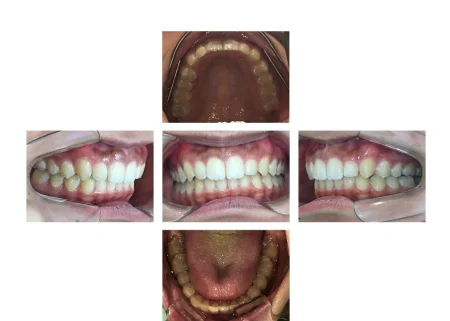

術後の経過・現在のご様子

歯がまっすぐきれいに並び、噛み合わせも安定してしっかり噛めるようになりました。

患者様にも「口元が気にならなくなり嬉しい」と非常にご満足いただきました。

現在は歯並びの後戻りを予防するための「保定装置」をご使用いただき、経過を拝見しています。